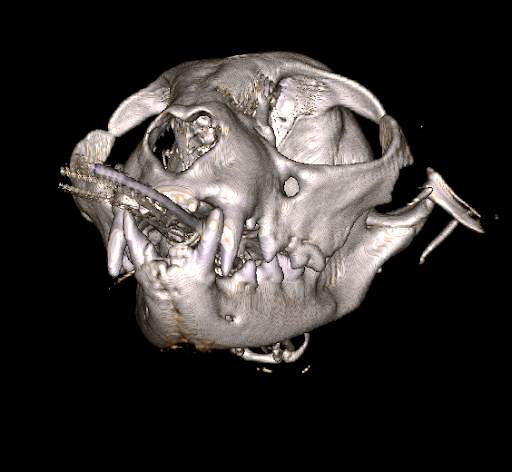

Figure 3. Three-dimensional reconstruction from cone computed tomography scan of a cat with a fracture of its zygoma bone. The fracture was the result of being attacked by a dog. The CBCT scan was completed at Animal Dental Care and Oral Surgery in Colorado Springs.

In addition, diagnostics including dental radiographs and/or a CT scan (cone beam CT scan or helical CT scan) are performed to assess the fracture site and teeth involved while under anesthesia. Animal Dental Care and Oral Surgery in Colorado Springs is proud to be the only veterinary practice in Colorado with cone beam computed tomography capability.